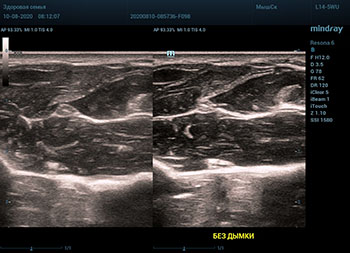

Ультразвуковое оборудование не отстает от современно тренда. В приборах серии Resona, компании Mindray, появилась новая функция постобработки изображения. Имя ей Dehaze. В переводе на наш родной язык – удаление дымки или рассеивание тумана. Инструмент позволяет корректировать интенсивность тумана или дымки. При этом сохраняется общий контраст и детализация картинки. Dehaze также позволяет проявлять детали снимка в гиперэхогенных зонах и снимать артефакты при чрезмерном усилении.

Готовый снимок или видео петля в формате DICOM несет в себе полное нативное изображение. Прибор позволяет, подобно легендарному фотошопу, удалить лишний «туман». Гиперэхогенный диффузный «засвет» изображения, из-за повышенного общего усиления, часто вредит обследованию. Однако без него некоторые вещи не видны. Показать гипоэхогенные участки и скрыть эхогенную дымку и позволяет Dehaze.